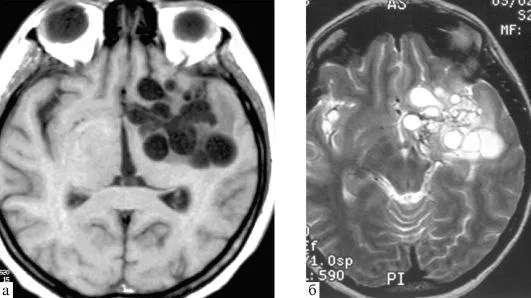

Множественные эхинококковые кисты в мозгу человека

Но вообще не до шуток когда мозг человека может превратиться в такое решето: